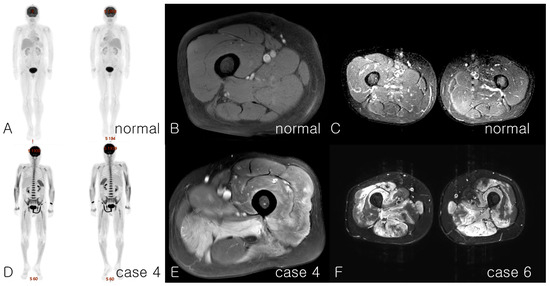

| MRI, involved muscles | Whole-body muscle: proximal and distal, upper and lower limbs | Only shoulder MRI checked: Proximal Arm, chest, back, neck | Whole-body muscle: proximal and distal, arm, leg, back | Diffuse upper and lower limbs | Proximal upper and lower | Proximal, upper and lower limbs, back | Whole-body muscle: proximal and distal, upper and lower limbs, back and chest | Proximal, upper and lower limbs, back | Whole-body muscle | Subtle myopathic change, upper and lower limbs | |